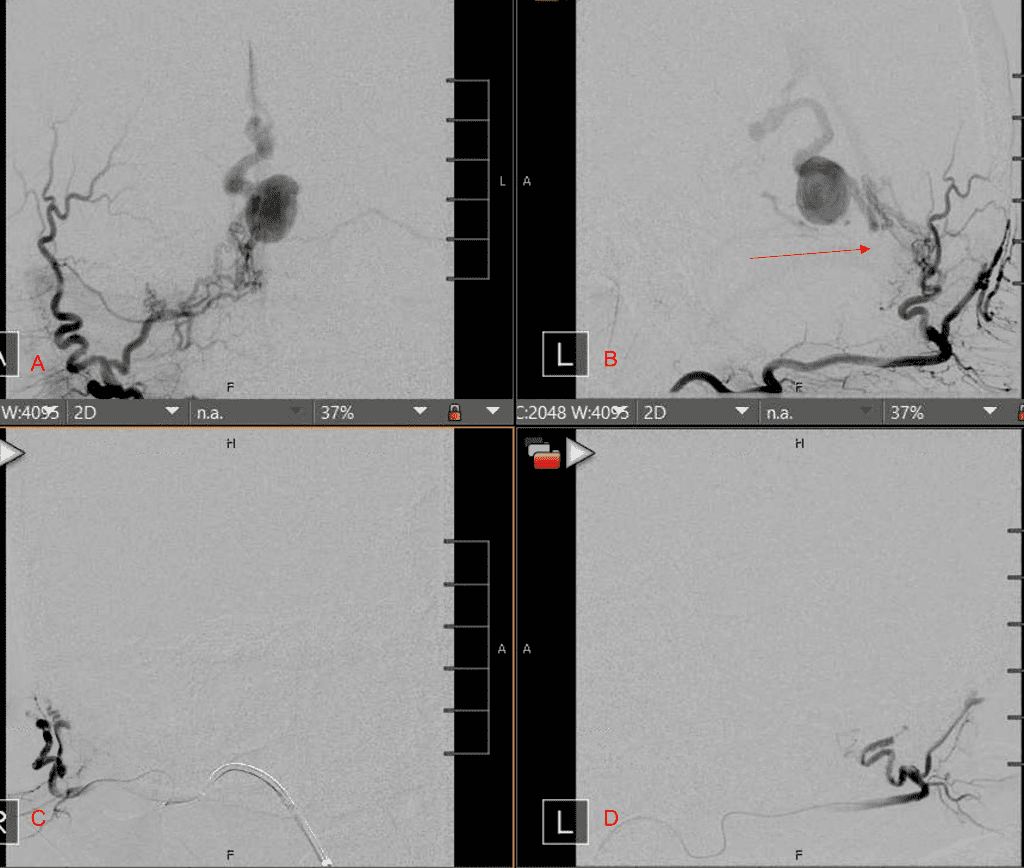

Figure 2. [A] Ruptured Varix/Aneurysm of the Deep Venous Posterior Fossa drainage and AV shunting (arrows) [B] Posterior Meningeal Artery Fistula [C] Right Middle Meningeal Artery Fistula [D] Post embolization Left Vertebral Angiogram demonstrates resolution of the high flow and pressure A-V Shunting following successful embolization with liquid embolic (NBCA).

Figure 3. Right ECA AP and Lateral angiograms Pre (A and B) and Post NBCA embolization (C and D) Demonstrate near complete obliteration of right Occipital and Middle Meningeal Artery Fistulas

Figure 4. Left ECA AP and Lateral angiograms Pre (A and B) and Post NBCA embolization (C and D) Demonstrate near complete obliteration of Left Occipital Artery Fistulas.